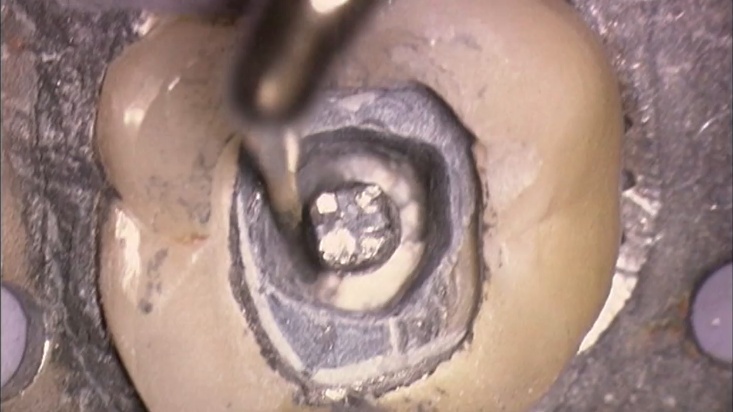

Сл. 37.37 Безбедно отстранување на леана надградба од коренскиот канал на горниот десен втор премолар.